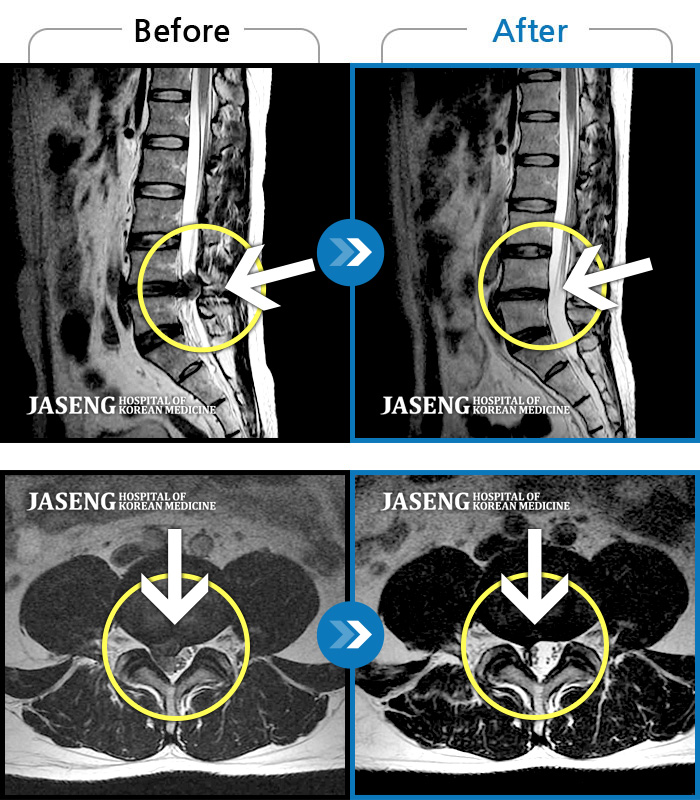

ȯںп Ǹ ǿ ԿǾ, ο ġ ۿ Ƿ ġḦ Ͻñ ٶϴ.